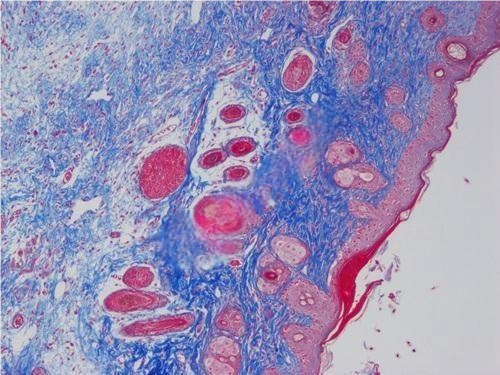

3.大鼠皮肤损伤masson